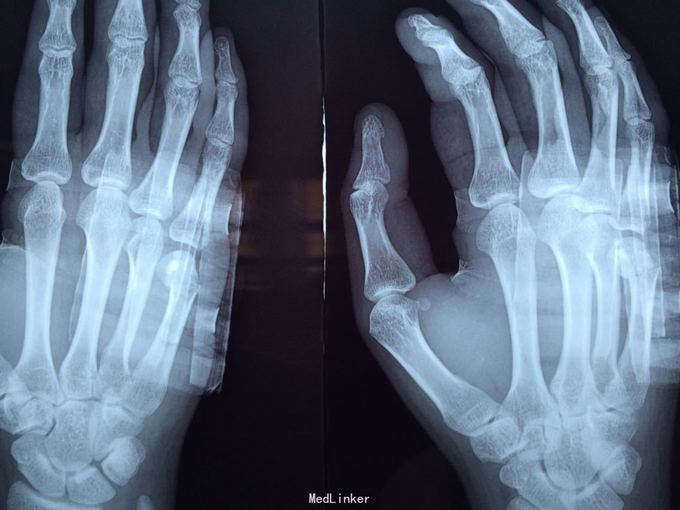

黄某某,男,29岁。 主诉:右掌第五节疼痛肿胀伴有活动受限2周余。 病史:患者16日前右手一拳打到墙上,致使右掌第五节疼痛,肿胀,活动受限,随即到骨伤科医院诊治,主诊医生拍X片后建议患者行手术治疗,但患者可虑到自己年轻,加上咨询了一些做医生的亲朋好友的意见,决定保守治疗。患者自诉当主诊医生听到患者不愿意做手术后,就建议行石膏固定治疗,当时就一个医生给患者进行手法复位,基本没有效果,但主诊医生照样行石膏固定。2周后遂来我院治疗,现患者右掌第五节疼痛,肿胀,活动受限,无其他不适。

查体检查:右掌第五节压痛明显,可扪及骨擦音,纵向叩击痛。

诊断:右掌第五节掌骨骨折(气滞血瘀) 处理:手法复位后行小夹板固定,口服接骨七厘片,5#/次,bid,隔两天换药。